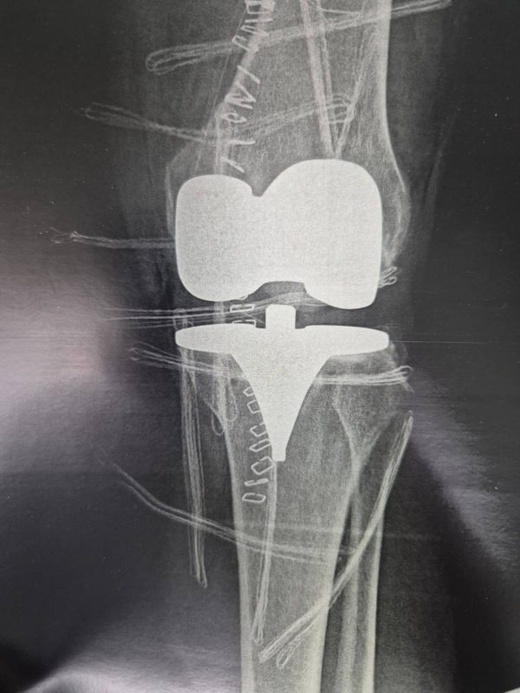

نجح فريق طبي وتمريضي متخصص في جراحة العظام والمفاصل، بالتنسيق مع طاقم الإنعاش والتخدير بالمستشفى الإقليمي الحسني في الناظور، في إجراء عملية جراحية دقيقة لاستبدال مفصل الركبة اليسرى بمفصل اصطناعي كامل، لسيدة في الستين من عمرها كانت تعاني من التهاب مزمن في المفصل نتيجة التآكل الكامل للغضروف.

العملية الجراحية أُنجزت تحت إشراف الدكتور جواد أمغار، أخصائي جراحة العظام والمفاصل، وبمشاركة فعالة من فريق التخدير بقيادة الدكتور عبد الواحد الوزاني. وتُعد هذه العملية سابقة طبية على مستوى المستشفى، كونها المرة الأولى التي يُجرى فيها استبدال مفصلَي الركبتين لنفس المريضة داخل هذا المركز الاستشفائي.

وكانت المريضة قد خضعت لعملية مماثلة على مستوى الركبة اليمنى قبل ثلاثة أشهر، وقد تكللت بالنجاح، مما شجع الطاقم الطبي على استكمال العلاج الجراحي واستبدال الركبة اليسرى أيضاً، لضمان استعادة تامة لقدرتها على الحركة.

المريضة كانت تعاني من تآكل شامل في الأسطح المفصلية لكلتا الركبتين، ما سبب لها آلاماً مزمنة وصعوبات شديدة في الحركة وصلت حدّ الإعاقة، ولم تفلح العلاجات الدوائية والمسكنات في التخفيف من حالتها، الأمر الذي جعل التدخل الجراحي الخيار الوحيد الممكن.